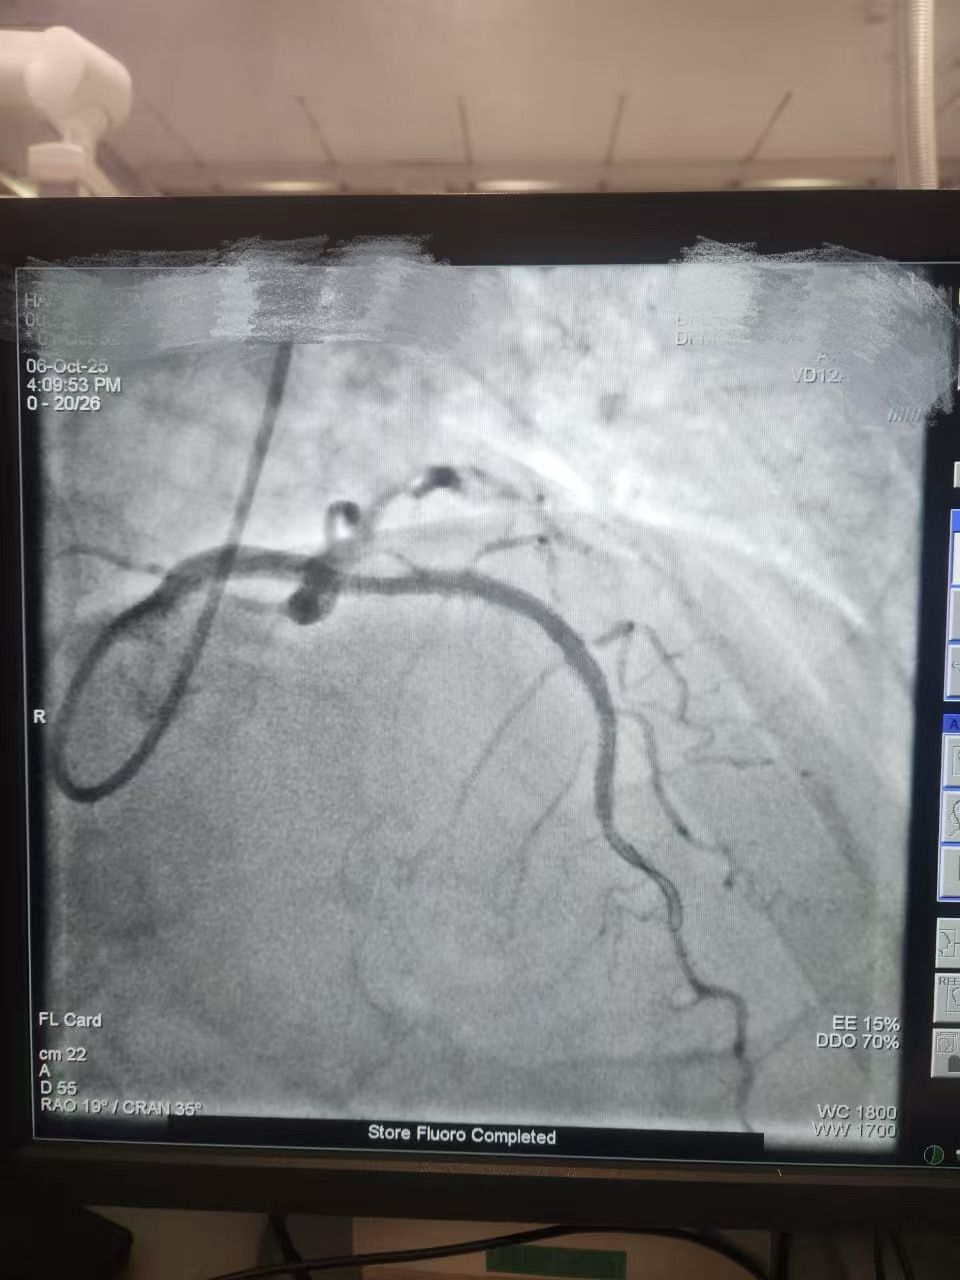

We are proud to share a successful clinical case from HMS Mirdif Hospital, UAE, where Dr. Mohamed Houcem Amiour and his exceptional Cath Lab team — Ambily Mathew, Aswathy S Babu, Geethanjali Rema Suresh, and Mathew Philip — successfully performed a PTCA to the LAD using Lepu Medical's Vesscrack Coronary IVL Balloon System.

To achieve optimal lesion preparation and stent expansion, the team skillfully combined Rotablator with Lepu's IVL, ensuring precise and effective calcium modification.